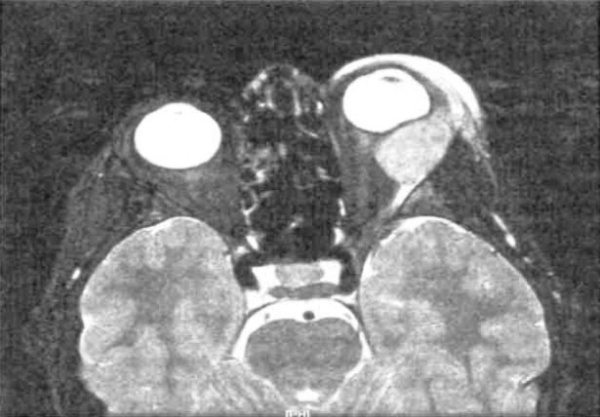

- КТ орбиты. На КТ-снимках лимфома орбиты имеет вид объемного образования неоднородной структуры. Опухоли бывают единичными или множественными, контуры новообразования имеют нечеткие границы. При запущенной форме болезни по данным КТ определяется разрушение костной стенки глазницы.

- МРТ орбиты. На МРТ-снимках определяются объемные новообразования неправильной формы, которые изоинтенсивны по отношению к мышцам орбиты и гиперинтенсивны относительно жировой клетчатки. Изредка визуализируется утолщение и инфильтрация глазных мышц.